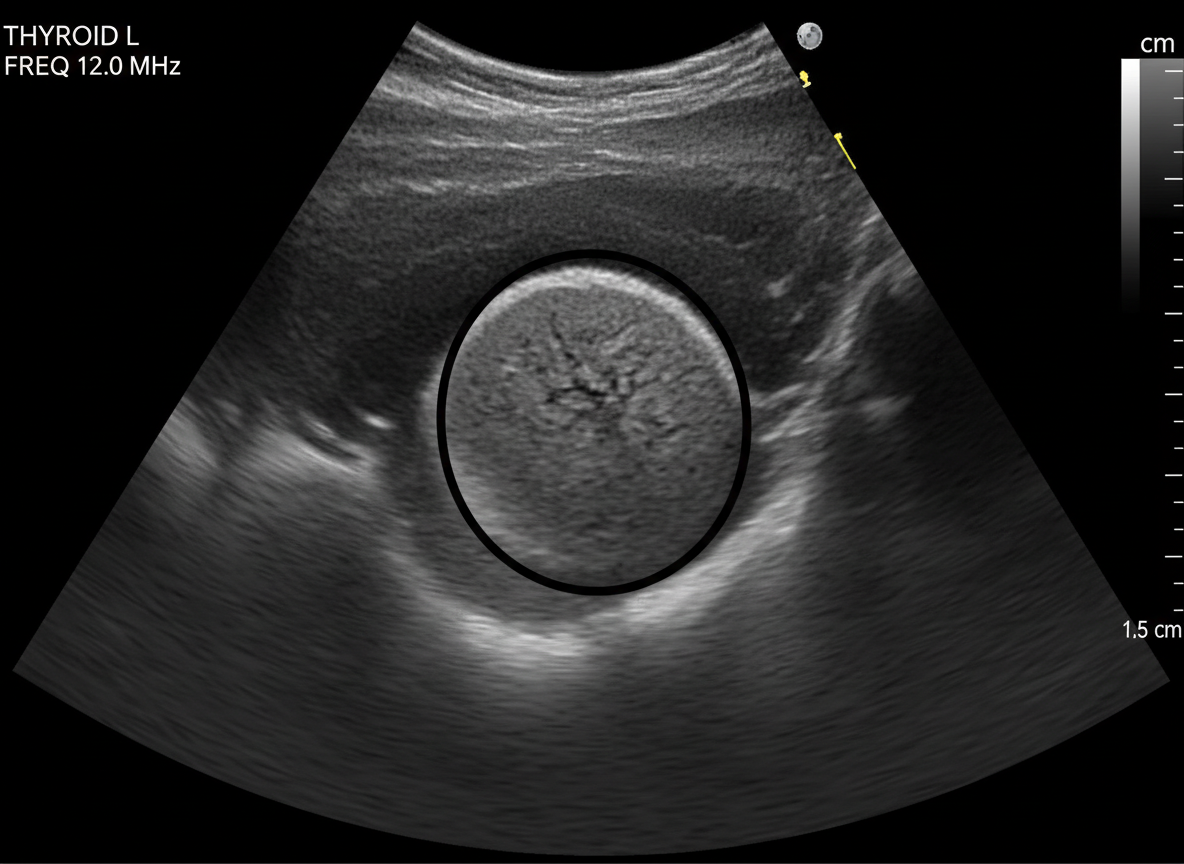

그 다음으로는 갑상선 초음파 검사를 하게 되는데,

이 초음파 검사를 통해

갑상선 결절의 유무와 크기, 모양 등을 확인할 수 있답니다.

초음파는 통증도 없고 아주 간단한 검사라서

부담 없이 받으실 수 있을 거예요.

만약 초음파 검사에서

의심스러운 결절이 발견된다면,